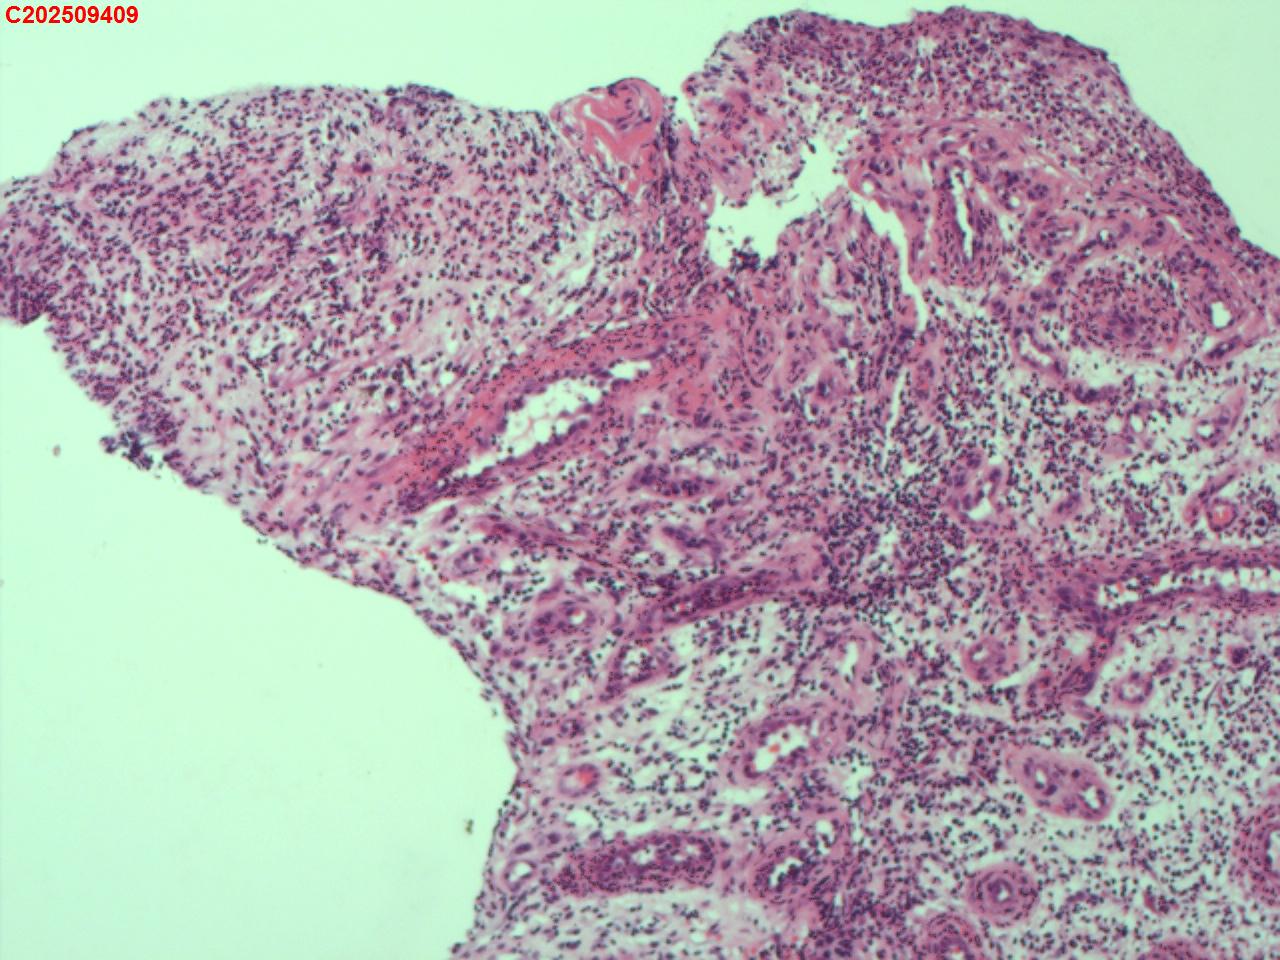

纤支镜咬检

性别年龄62岁临床诊断社区获得性肺炎,肺占位性病变带除外

一般病史胸部CT:双肺可见多发斑片状、结节状高密度影,右肺上叶及左肺下叶病灶内见多发空洞,右侧少量胸腔积液。

标本名称纤支镜咬检

大体所见纤支镜:气管通畅,隆突锐利。右肺主支气管通畅,右肺上叶见少量痰液,负压吸引后见上叶开口干酪坏死物质附着,上叶各段级支气管通畅未见新生物及坏死物质,中叶、下叶背段支气管通畅,下叶基底段见新生物阻塞气道,粘膜无充血。左肺主支气管、上叶、下叶及各段级支气管通畅,粘膜无充血,未见新生物及坏死物。

考虑:支气管炎性息肉